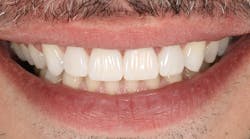

The patient requested an esthetic improvement of his anterior region. He was not happy with the position of his central incisors. After an old orthodontic treatment, a misalignment had developed and needed to be corrected using minimally invasive methods (figure 1).

A follow-up examination was performed 10 days after the placement. The tooth structure had rehydrated during that time, allowing me to assess whether the veneer had integrated successfully. The patient and I were both very pleased with the esthetic result. The visual impression of the anterior front is beautiful and harmonious. The dainty veneer looks completely natural and unnoticeable (figure 14).